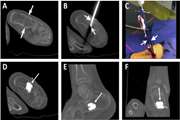

Treatment of a calcaneal unicameral bone cyst by percutaneous CT guided cement injection using a double needle technique: A case report 1403/12/01 - 11:11